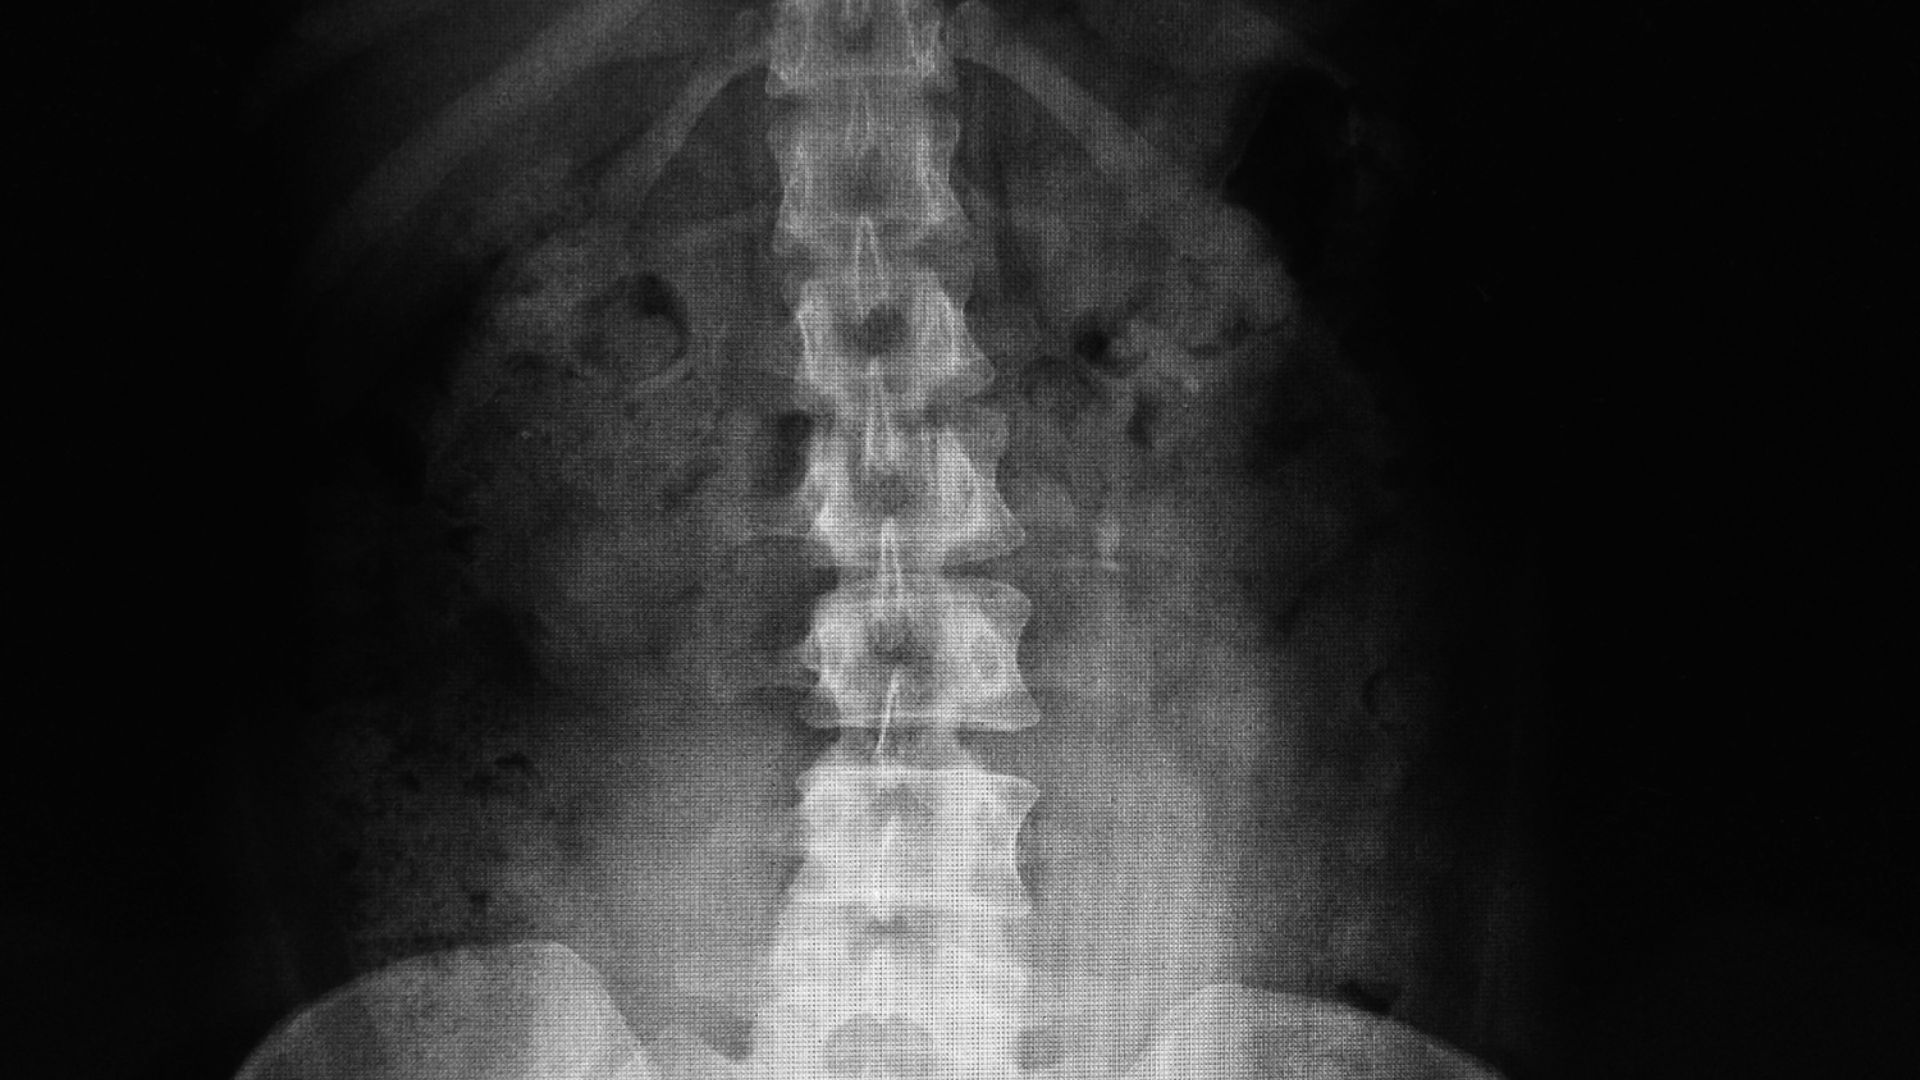

X-quang cột sống thắt lưng là kỹ thuật sử dụng tia X để tạo hình ảnh các đốt sống từ L1 đến L5, khe gian đốt sống và các cấu trúc xương liên quan. Đây là phương tiện chẩn đoán hình ảnh cơ bản, có vai trò quan trọng trong đánh giá ban đầu các bệnh lý vùng thắt lưng.

Tia X xuyên qua cơ thể và bị hấp thụ ở các mức độ khác nhau tùy theo mật độ mô. Xương hấp thụ tia X nhiều hơn mô mềm, do đó hiện lên rõ ràng trên phim chụp. Nhờ vậy, bác sĩ có thể quan sát được hình thái, vị trí và cấu trúc của các đốt sống thắt lưng, bao gồm thân đốt, mỏm gai, mỏm ngang và các khe gian đốt.

X-quang cột sống thắt lưng cho phép phát hiện nhiều bất thường quan trọng:

- Thoái hóa cột sống (gai xương mọc ra từ thân đốt, hẹp khe gian đốt sống, dày xương dưới sụn).

- Gãy, lún hoặc xẹp đốt sống (thường do chấn thương hoặc loãng xương).

- Trượt đốt sống (thân đốt sống trượt ra trước, sau hoặc sang bên, có thể kèm theo hở eo).

- Cong vẹo cột sống (vẹo, ưỡn, gù bất thường ở vùng thắt lưng).

- Dị dạng bẩm sinh của đốt sống (như thắt lưng hóa S1, cùng hóa L5, gai đôi, rối loạn chuyển tiếp).

- Một số dấu hiệu gợi ý viêm, nhiễm trùng (lao cột sống), u xương hoặc di căn.

Những hình ảnh này giúp bác sĩ xác định nhanh chóng các vấn đề cơ học liên quan đến xương, từ đó định hướng điều trị phù hợp. Tuy nhiên, X-quang cột sống thắt lưng không đánh giá được chi tiết mô mềm như đĩa đệm, dây chằng, rễ thần kinh hay tủy sống. Trong các trường hợp nghi ngờ thoát vị đĩa đệm, chèn ép thần kinh hoặc tổn thương mô mềm, bác sĩ thường chỉ định thêm MRI hoặc CT scan để có cái nhìn toàn diện hơn.